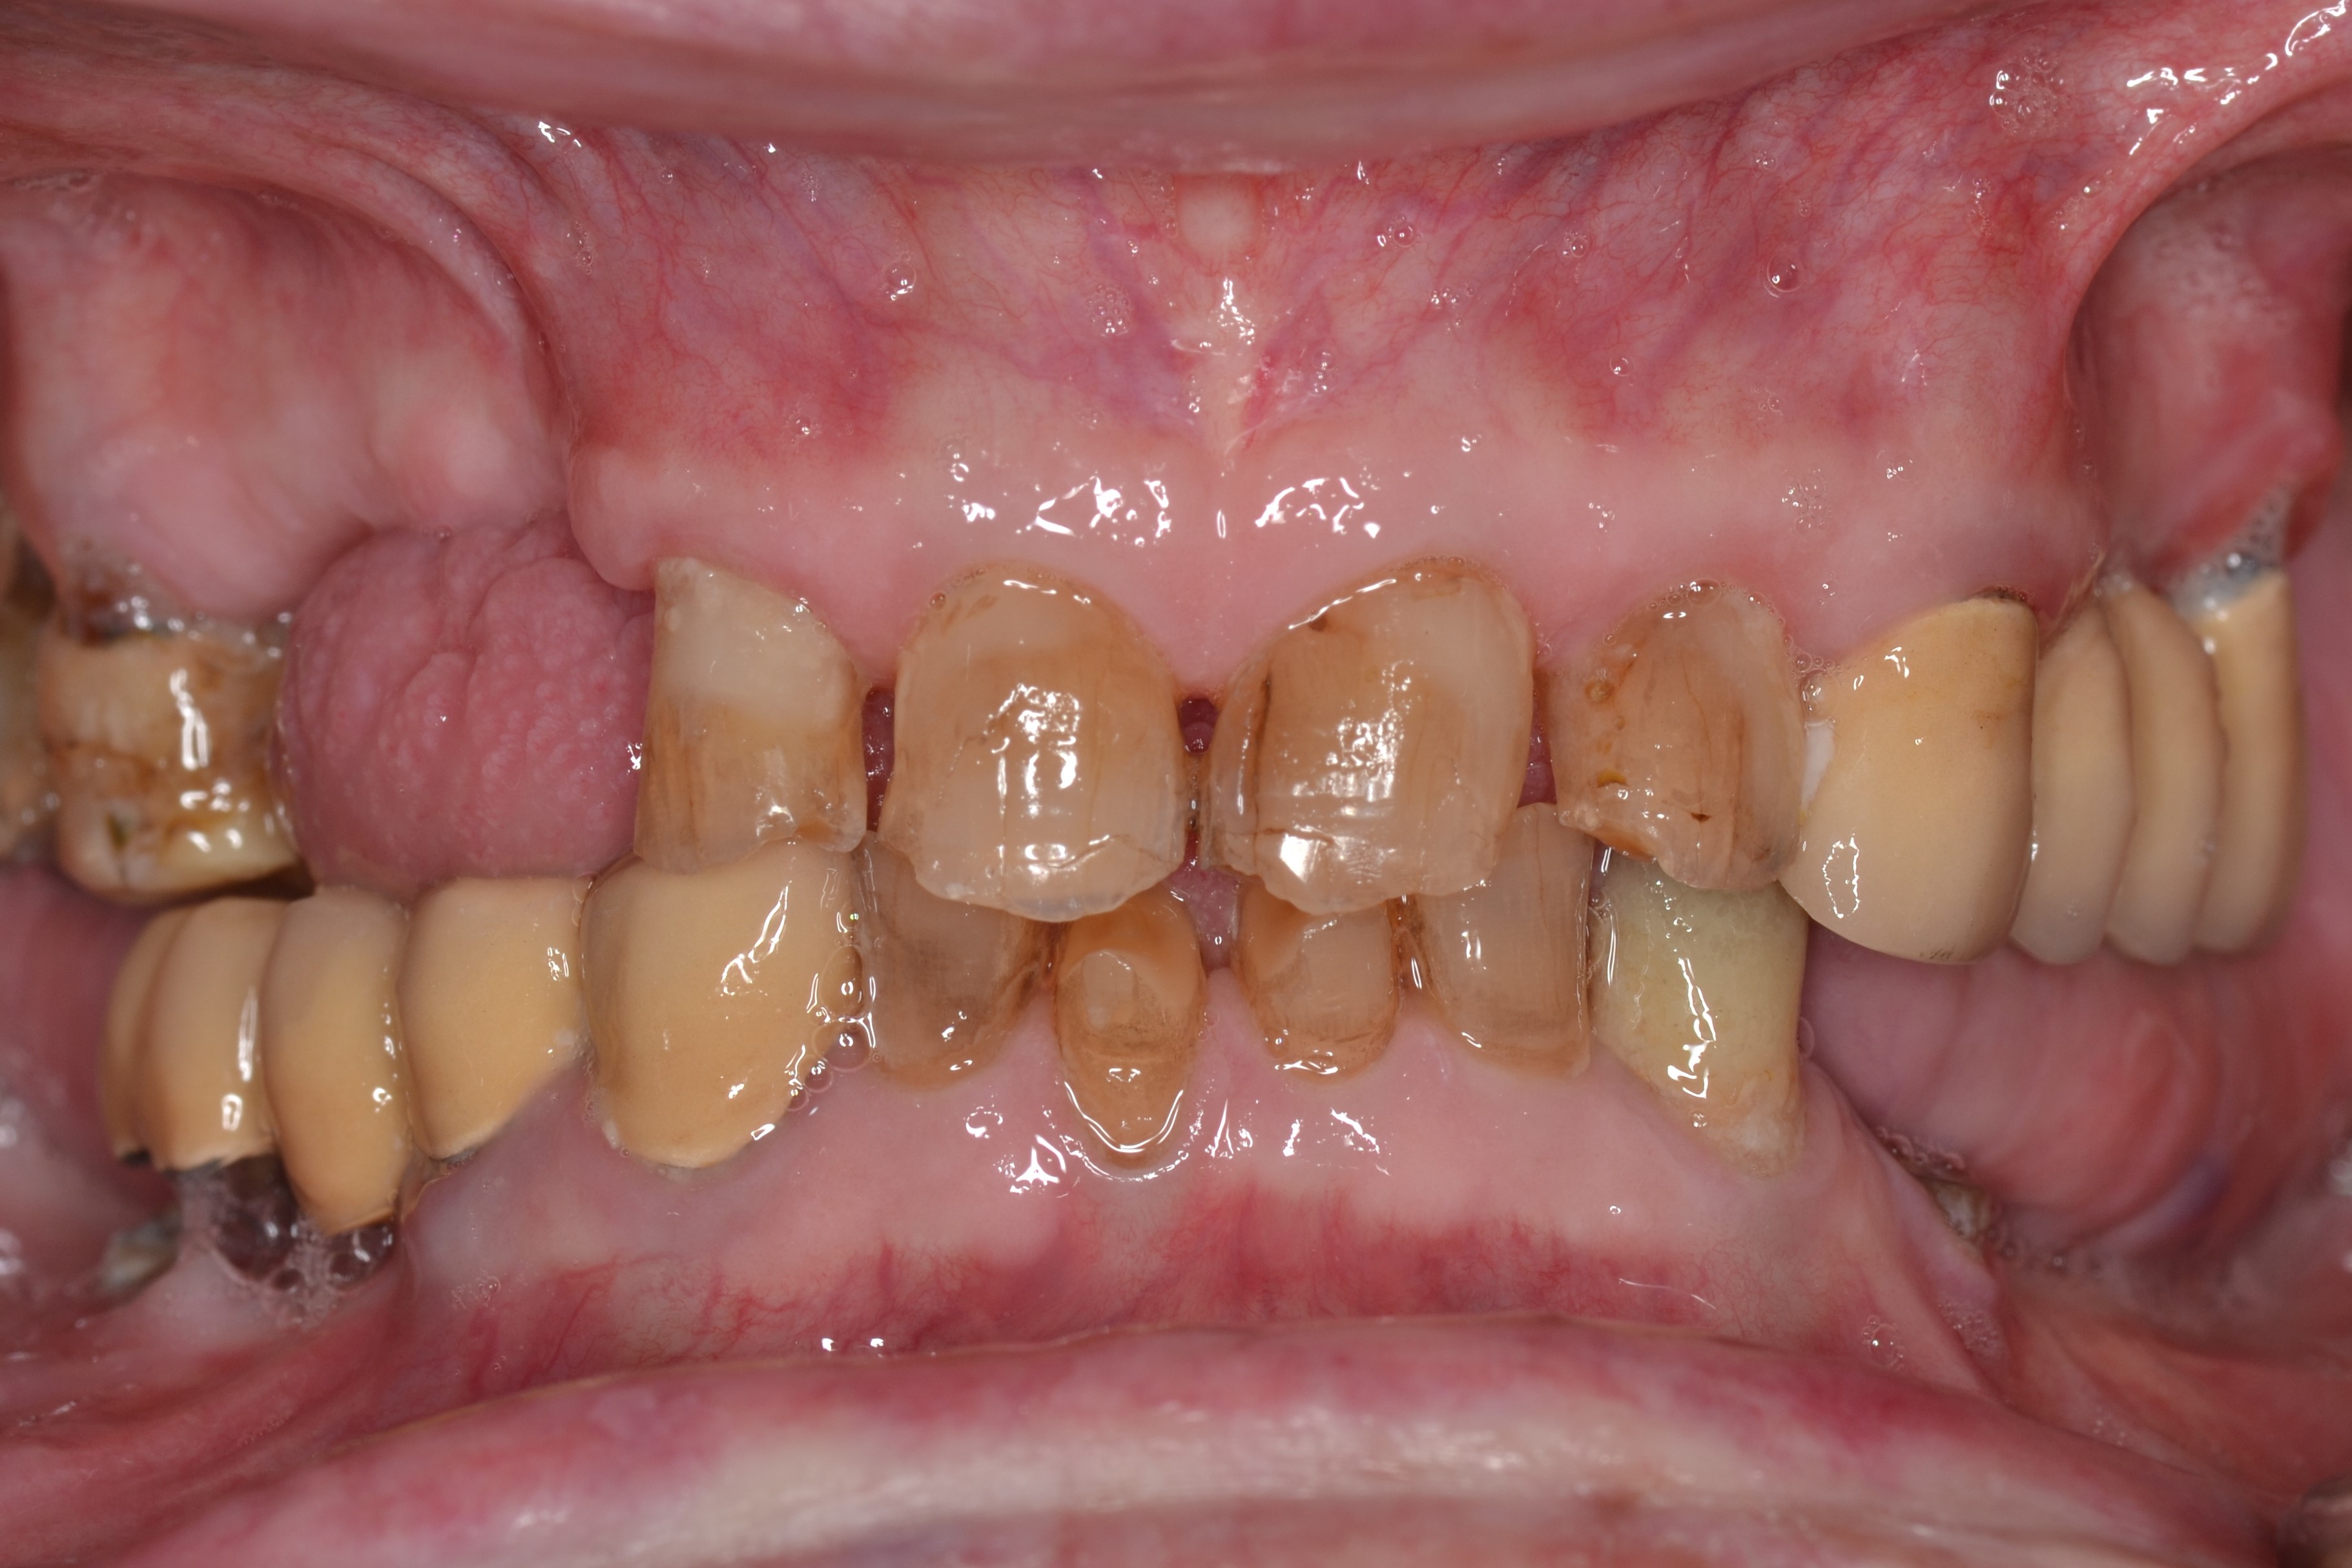

This 60-years old patient was missing a few teeth in his upper right jaw.The remaining teeth were mobile and tender when eating.

We extracted the remaining upper teeth and made him a full acrylic denture.